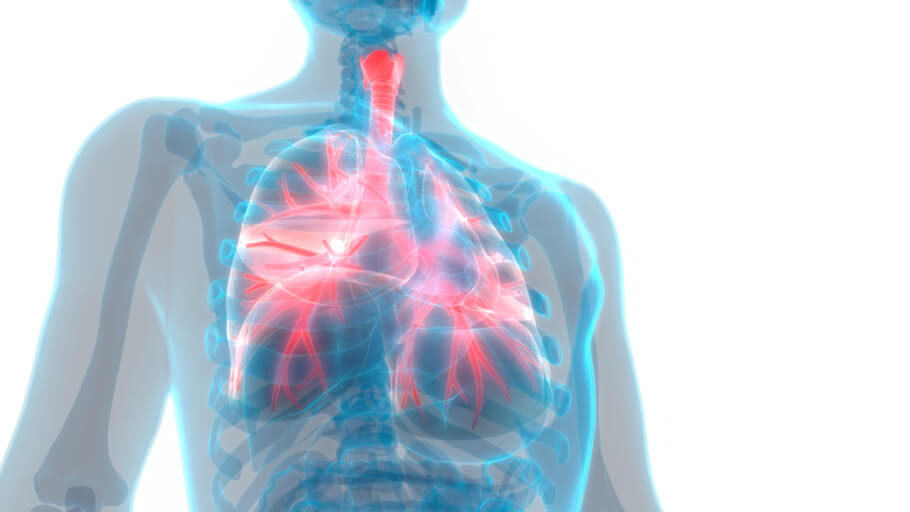

폐렴초기증상의 경우 가슴통증과 같은 문제도 제공할 수 있습니다. 이는 호흡할 때 주로 흉통이 심해진다는 특징 때문이기도 한데요. 이는 폐를 둘러쌓고 있는 흉막에 염증이 생기기 때문에 발생하는 것입니다.

6) 호흡곤란

폐에 발생하는 성인 폐렴 증상인 만큼 해당 문제로 인해 호흡곤란을 느낄 수 있습니다. 예전에 비해서 호흡 자체에 불편함을 느끼고 통증이 느껴지는 경우도 있습니다.